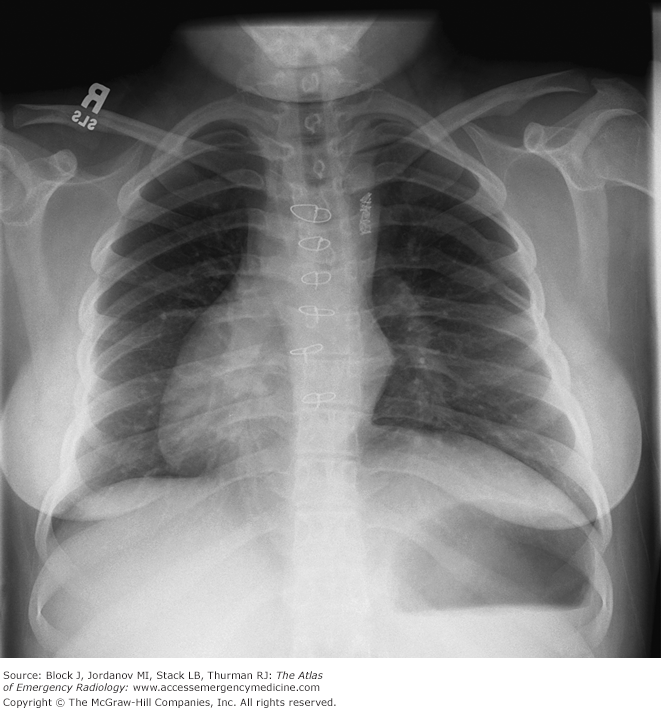

Situs inversus totalis

Dextroposition – heart points more to right

Dextrocardia with situs inversus – heart is completely on right side

Situs inversus totalis – heart and all organs are mirrored from normal configuration